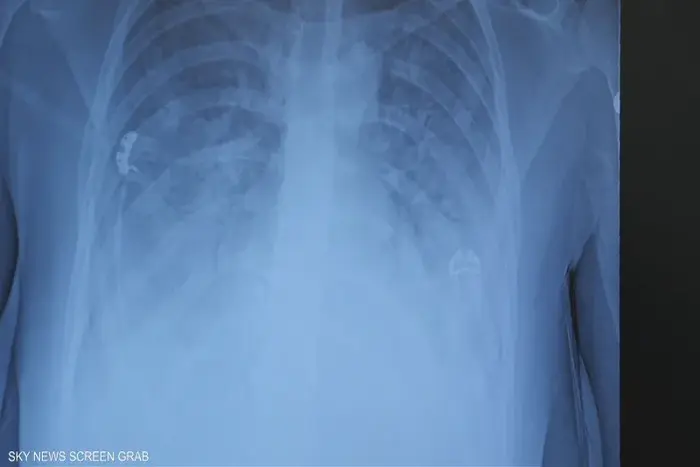

السجائر الإلكترونية مضرة بخلايا الرئة

اكتشف علماء بجامعة كاليفورنيا (ريفرسايد) أن تسخين المكون الرئيسي لمعظم سوائل السجائر الإلكترونية قد يؤدي إلى تكون مادتين كيميائيتين سامتين مضرتين بخلايا الرئة.